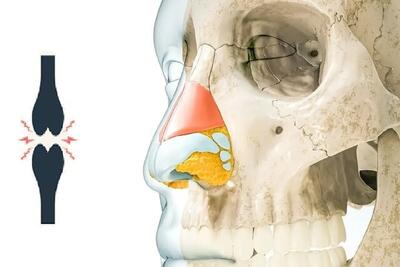

راهکارهای طب سنتی برای کاهش صدای مفاصل ! - سبک ایده آل

مصرف خوراکیهای ضد نفخ و همچنین ماساژ با روغن زیره و پرهیز از غذاهای نفاخ به کاهش صدای مفاصل کمک میکند.